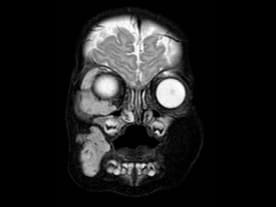

Charley-Jean - aged three months before treatment.